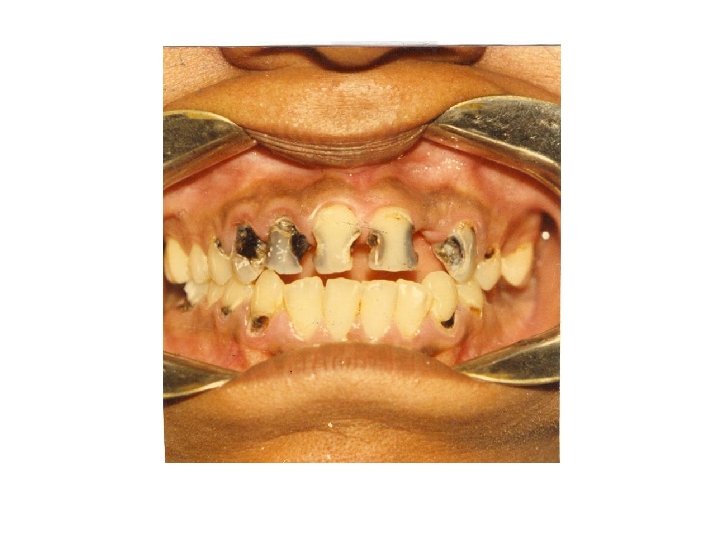

CARIES SUSCEPTIBILITY OF INDIVIDUAL TEETH • • • Upper and lower first molar 95% Upper and lower second molar 75% Upper second bicuspid 45% Upper first bicuspid 35% Lower second bicuspid 35% Upper central and lateral incisor 30% Upper cuspids and lower first bicuspid 10% Lower central and lateral incisor 3% Lower cuspids 3% Teeth farthest back in the mouth are more frequently carious. Caries susceptibility of individual tooth surface occlusal > mesial > buccal > lingual

ACUTE DENTAL CARIES - Rapid clinical course & early pulp involvement - Process rapid little time for deposition of sec. dentin. Dentin stained a light yellow - Rampant caries, affecting deciduous dentition nursing bottle caries - Commonly 4 maxillary incisors followed by first molar and then cuspids - Absence of caries in mandibular incisors distinguished from ordinary rampant caries